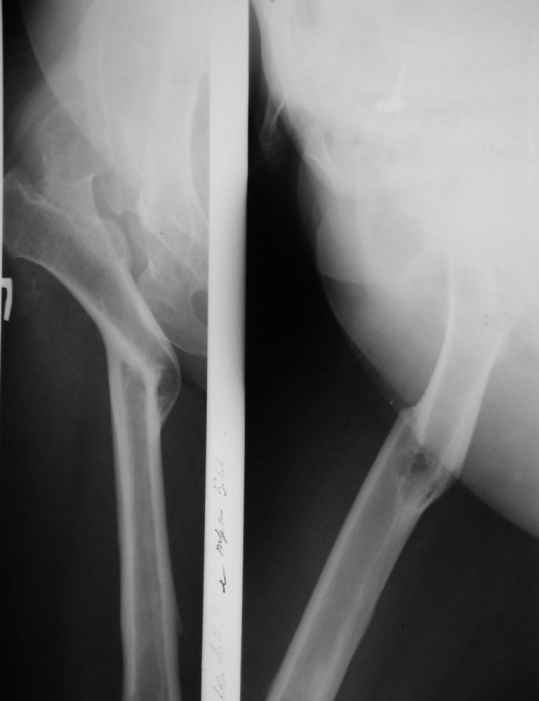

Я вижу три возможны варианта в этом случае. Самый простой--артродез. Второй--одновременная остеотомия бедра и фиксация его протезом на длинной ножке с покрытием по всей длине. Лучше всего использовать модулярный протез вроде Depuy S-ROM или Stryker Restoration. Они дадут наибольшее количество вариантов для работы с сильно деформированным бедром. Третий вариант--остотомия с фиксацией пластиной типа blade plate или proximal femoral locking plate, а потом, когда заживёт остеотомия, удаление пластины и более "стандартное" протезирование. На мой взгляд, второй вариант наиболее приемлемый, если у вас есть доступ к вышеупомянутым протезам.

мы бы выполнили THA с укорачивающей, корригирующей резекцией на уровне деформации, тип ножки на ваш выбор, по литературе : лучше AML или Цваймюллер, по нашему опыту - подойдет Corail, если не уверены в ротационной стабильности -добавьте небольшую деротационную пластину (1/3 трубки по 3 винта с каждой стороны подойдет)

Уважаемый Андрей, ситуация не простая, нет обзорной Р-графии таза, поэтому сложно провести правильное планирование операции. Тем не менее, при планировании операции вертлужный компонент я бы установил в анатомическое положение. В отношении ножки - может быть два решения. Мое предпочтение - (операция типа Paavilaanen'a) поперечная остеотомия бедра на уровне чуть выше деформации, установка ножки Вагнера, скорее всего 190 мм, хотя возможно удастся обойтись и конической ножкой, это зависит от необходимой компенсации длины ноги. Продольная остеотомия б/вертела с последующей фиксацией к диафизу бедра с натяжением мышц. Есть и другой вариант - укорачивающая остеотомия в зоне деформации бедра с установкой ножки со стороны шейки. Мы делали и то и другое, первый вариант проще. В этой операции есть масса нюансов и нужно иметь опыт операций при дисплазии ТБС.

Был у нас подобный случай

Выполнена одномоментная коррекция деформации, эндопротезирование DePyu Pinnacle-AML. Пластинка с деротационной целью. При использовании ножки с прямоугольным сечением, думаю, можно и без нее.

Уважаемый Андрей! Действительно сложно спланировать операцию без обзорного снимка таза, а так же рентгенограмы бедра в аксиальной проекции. По поводу реконструкции бедренной кости могу предложить следующие варианты опробированные на практике (если есть необходимость пришлю Р-граммы).

-Клиновидная остеотомия бедра на вершине деформации, с углом открыты внутрь. Это позволит выпрямить бедро, добиться полной адаптации обоих фрагментов. Использование ножки Вагнера не позволит фиксировать проксимальный отломок и потребуется какая то дополнительная фиксация, возможно пластиной.

-То же самое с использованием ножки Helios (Biomed) позволит выполнить вполне качественный остеосинтез (ножка из двух частей и позволяет оптиально зафиксировать оба фрагмента), к тому же с возможностью блокирования. Поэтому дополнительной фиксации не потребуется.